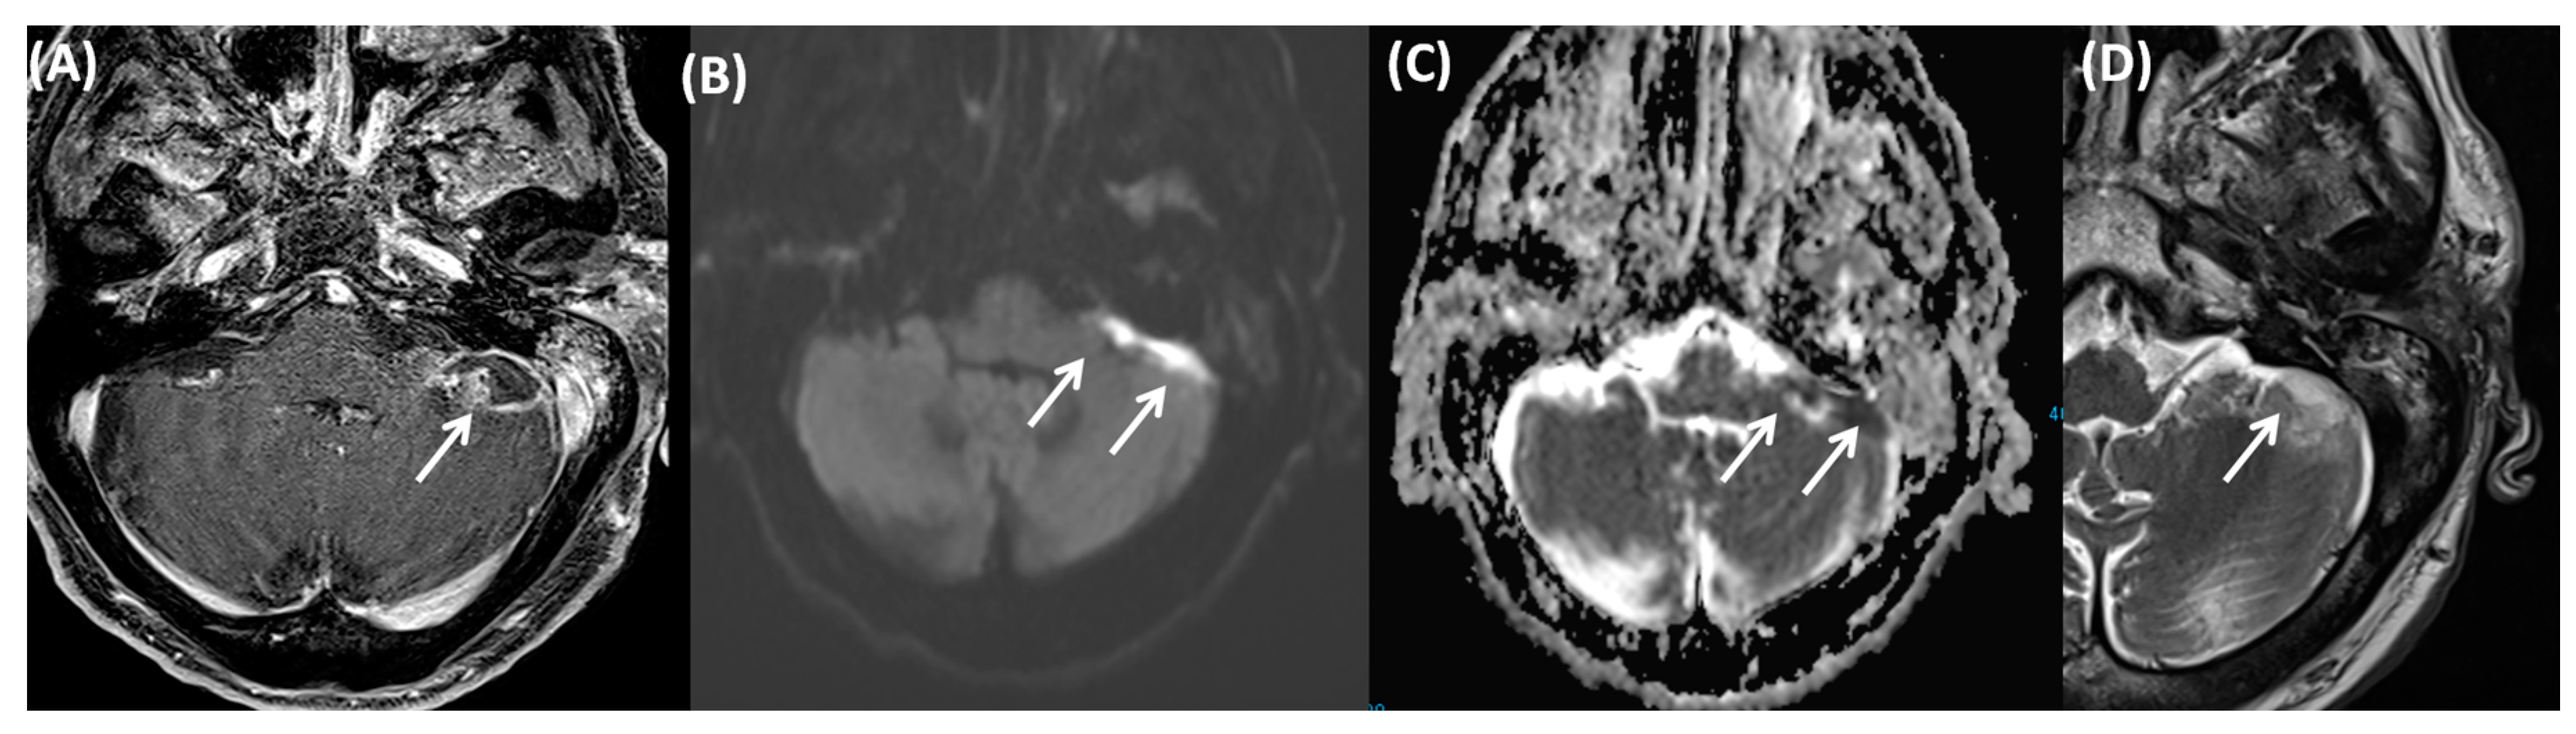

4.3. Cerebral Venous Sinus Thrombosis

4.4. Otitic Hydrocephalus

4.5. Ramsay Hunt Syndrome

5. Conclusions